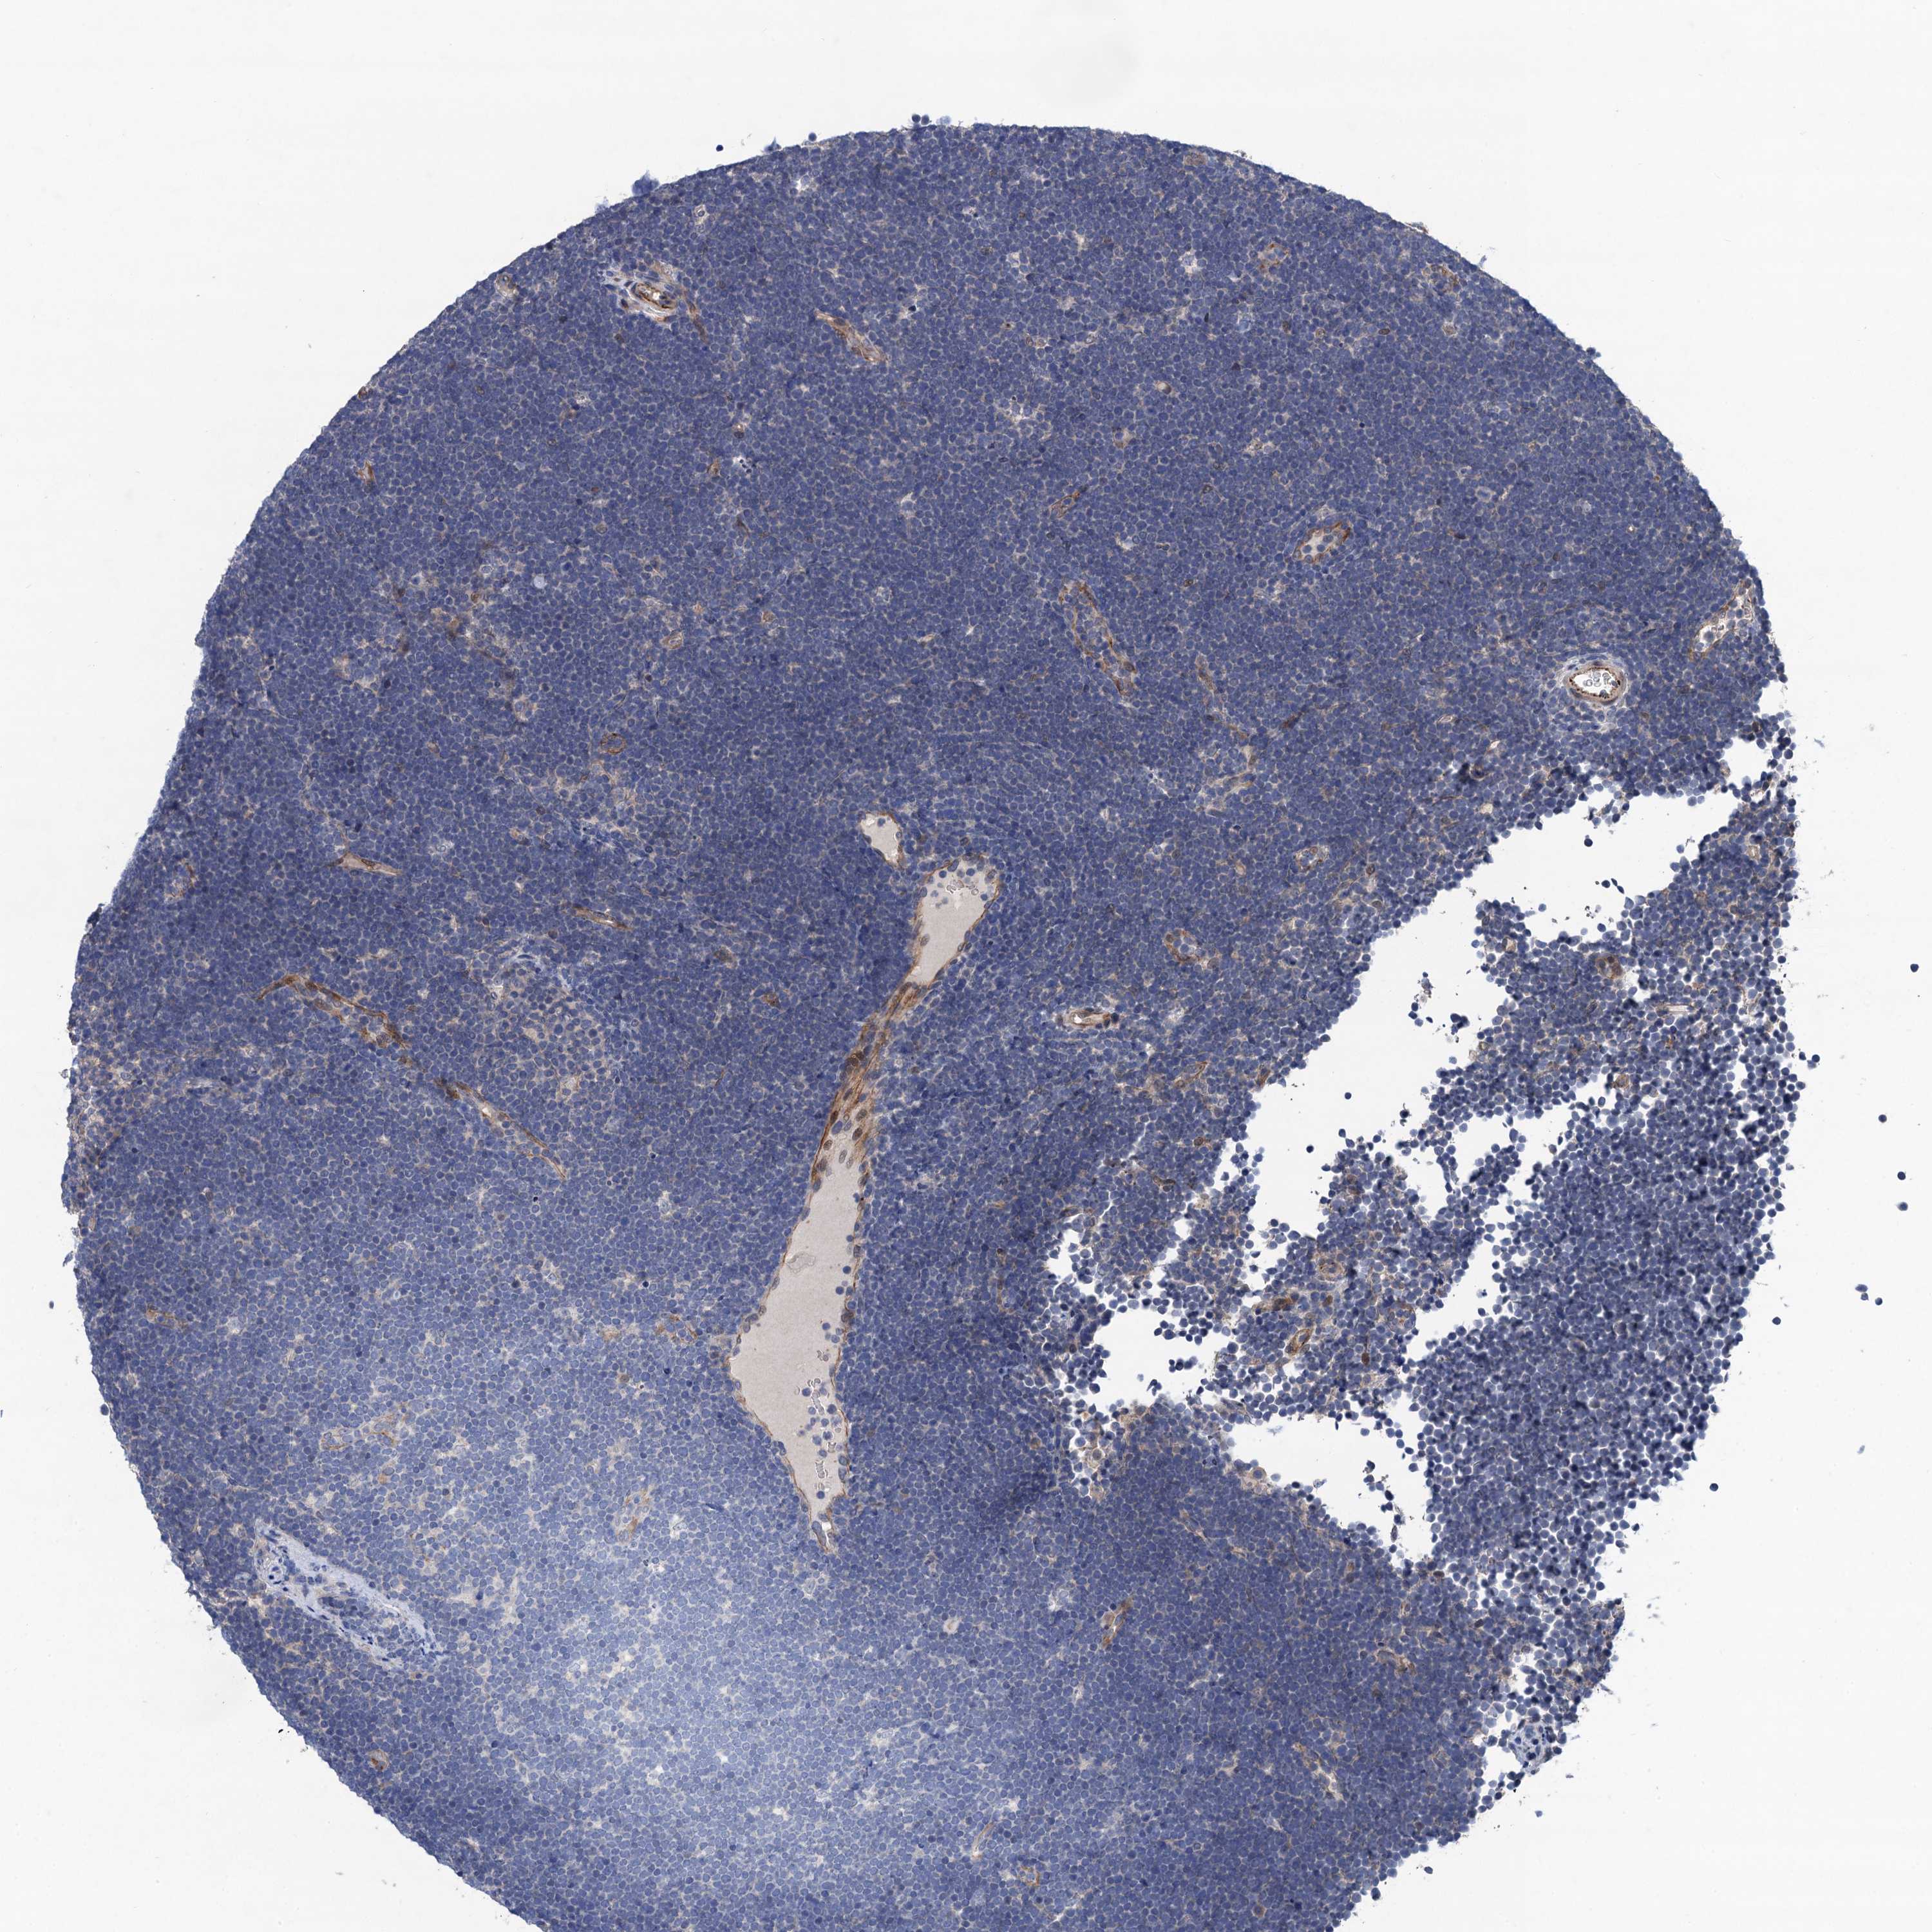

CANCER LYMPHOMA Show tissue menu

LYMPHOMA - Protein expressioni

A mouse-over function shows sample information and annotation data. Click on an image to view it in a full screen mode. Samples can be filtered based on level of antibody staining by selecting one or several of the following categories: high, medium, low and not detected. The assay and annotation is described here.

Each image is clickable and will lead to virtual microscopy that enables deeper exploration of all samples and also displays staining intensity scores, fraction scores and subcellular localization as well as patient and tissue information for each sample.

Antibody HPA041229

Staining

High

Medium

Low

Not detected

Intensity

Strong

Moderate

Weak

Negative

Quantity

>75%

75%-25%

<25%

None

Location

Nuclear

Cytoplasmic/membranous

Cytoplasmic/membranous,nuclear

Hodgkin's disease, NOS

Malignant lymphoma, non-Hodgkin's type, High grade

Malignant lymphoma, non-Hodgkin's type, Low grade